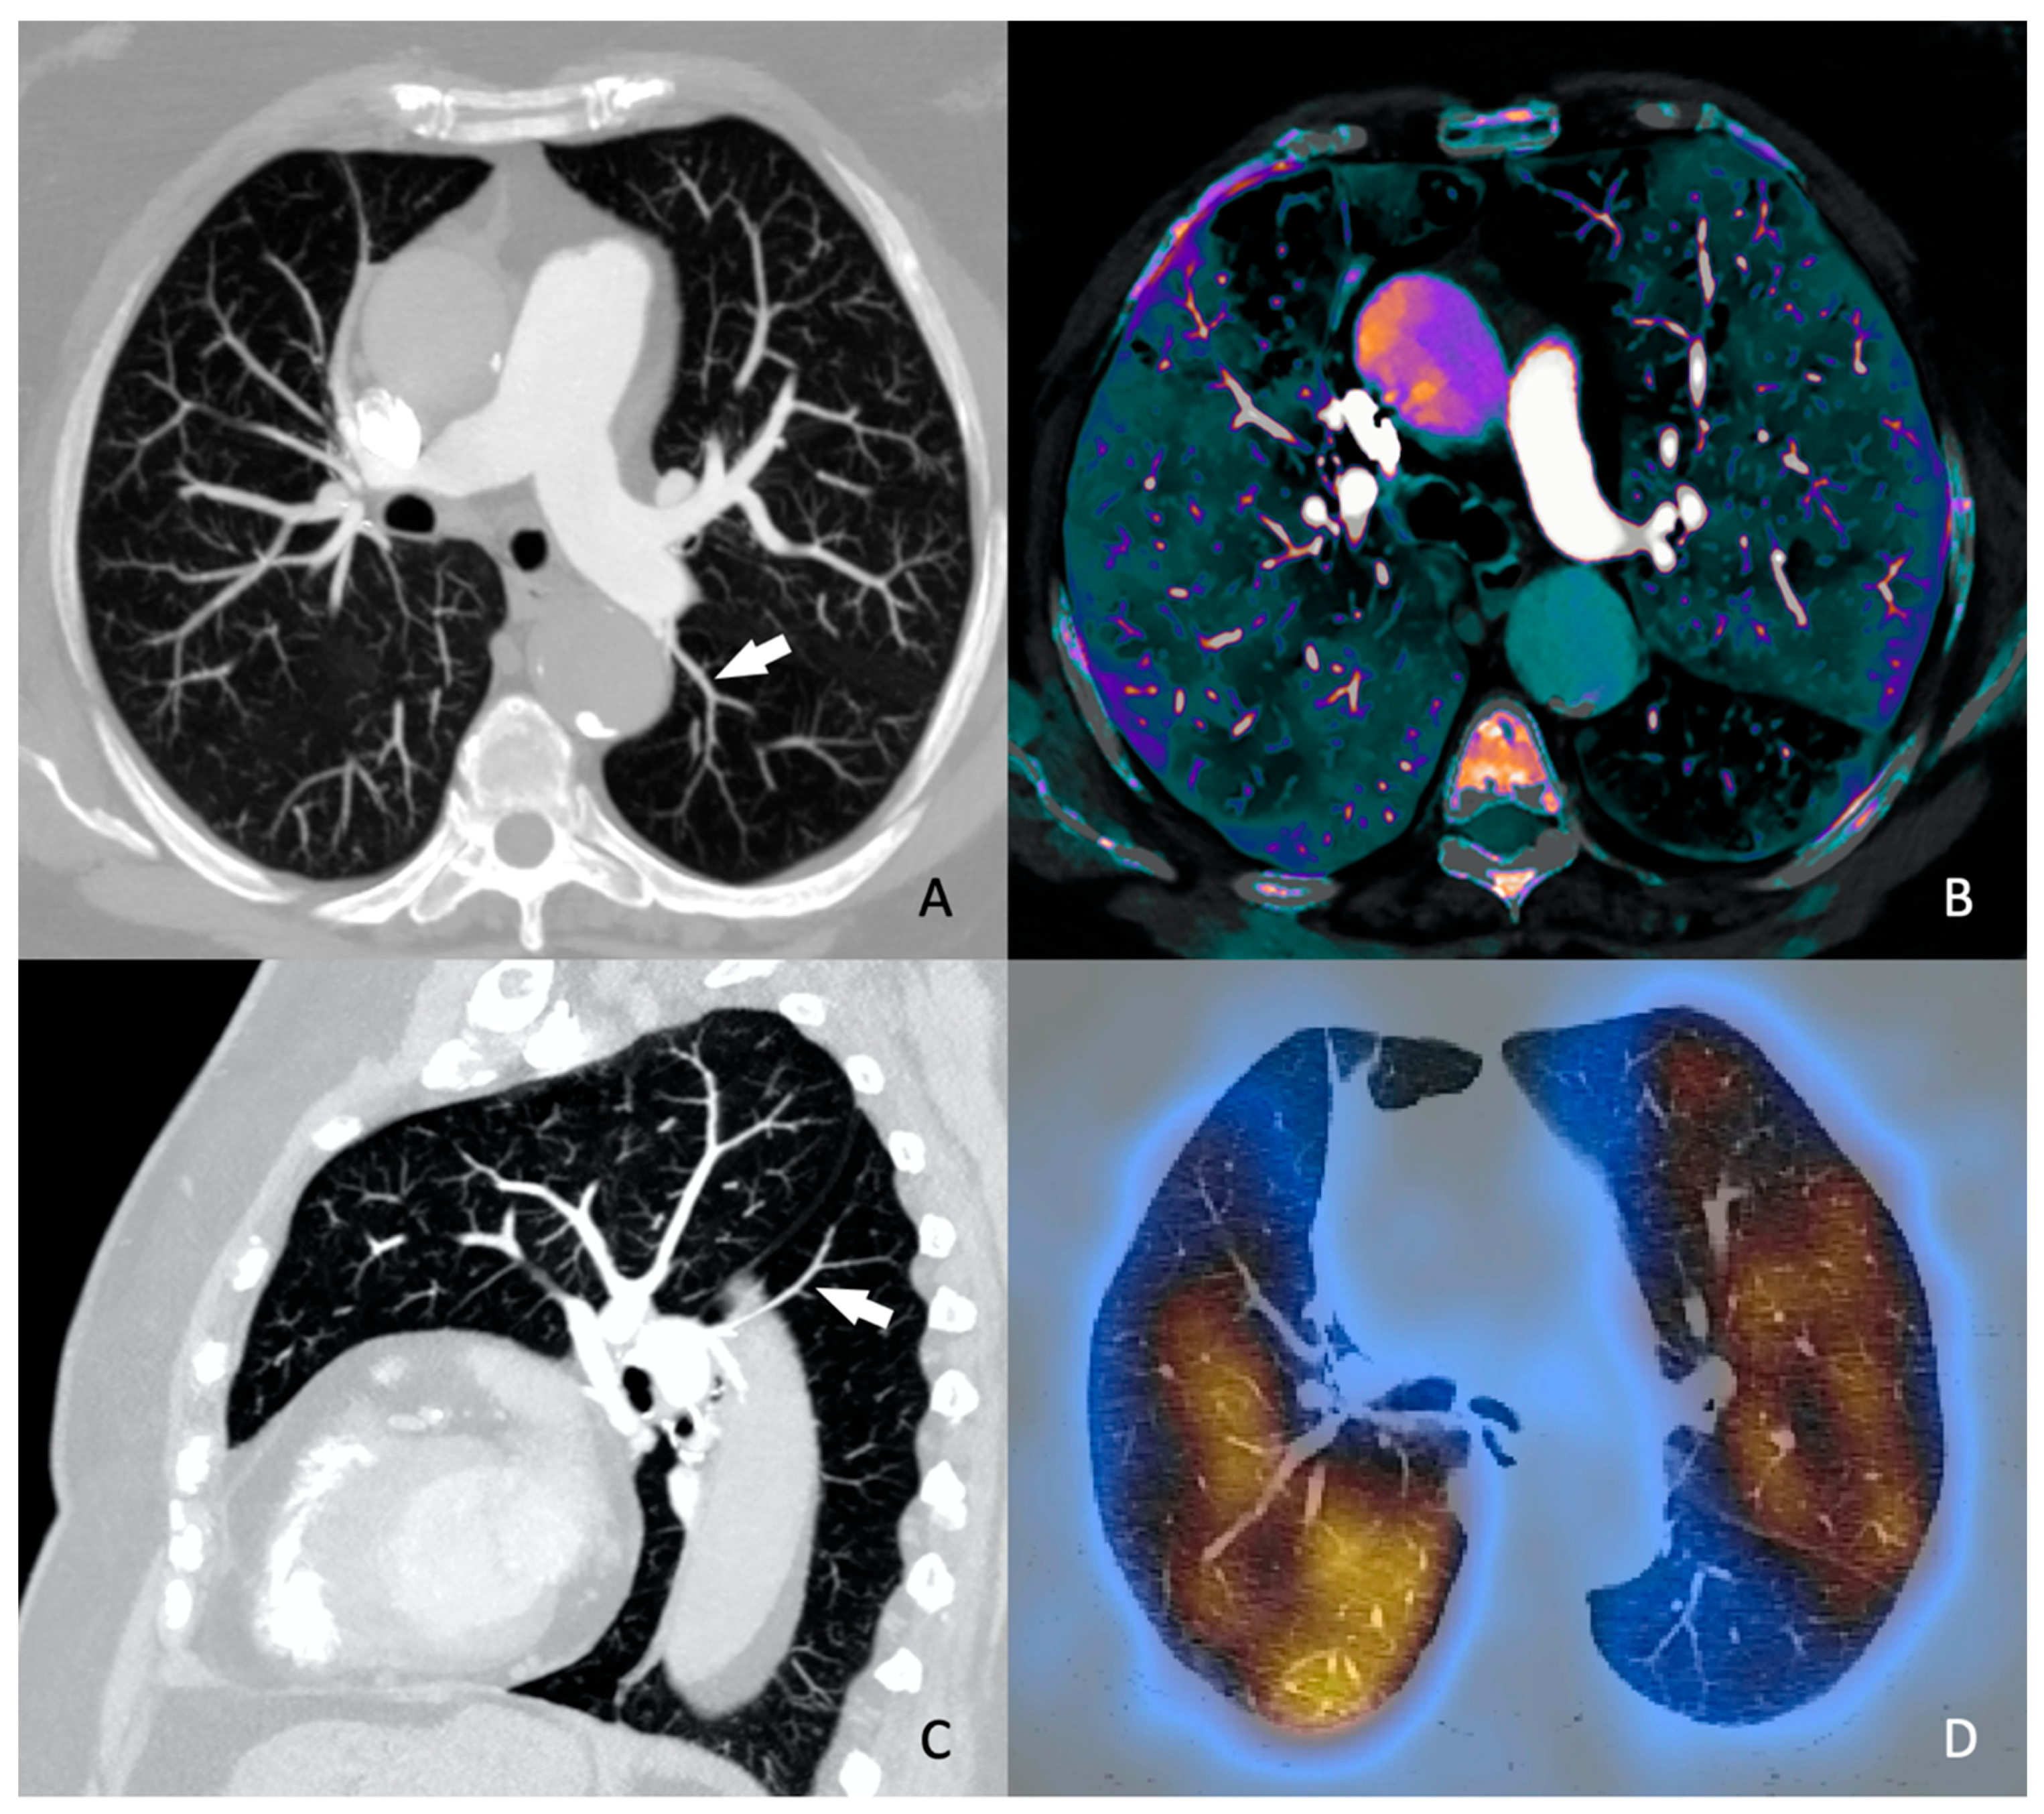

Conversely, the meta-analysis by Meinel et al. [12], published in 2015, reviewed 49 studies involving 13,162 patients and concluded that the axial RV/LV ratio should be included in all reports (Figure 1). An axial RV/LV ratio greater than 1 is associated with a 2.5-fold higher risk of all-cause mortality and adverse outcomes, and a 5-fold higher risk of PE-related mortality. This finding contrasts with Kang et al.'s results. Different authors propose a cut-off range varying from 0.9 to 1.5, which can lead to potentially conflicting conclusions. However, Meinel et al. provide a detailed analysis of the relationship between the axial RV/LV diameter ratio and all-cause mortality risk, stratified by sources of heterogeneity, resulting in a robust conclusion. In clinical practice, especially in the urgent context where CTPA studies are conducted, the ratio of right to left ventricular diameter is a measure that is easy to obtain, unlike ventricular volumes or four-chamber reconstructions. Therefore, Meinel's recommendation is deemed appropriate. While the parameters suggested by Kang et al. are undeniably valuable, their acquisition post-acute event requires practice, time, and skill, which may not be feasible in emergency settings.

Figure 1. 56 years old woman diagnosed with acute pulmonary thromboembolism. Axial RV/LV diameter ratio >1 measured at the base of both ventricles (black arrows).